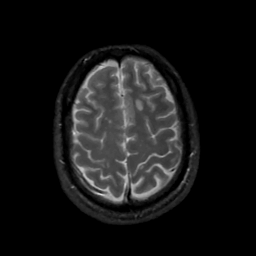

MR Study #1, February 10, 1991 -- Slice #40

[Home][Help][Clinical][Tour 1][Tour 2] Slice 40